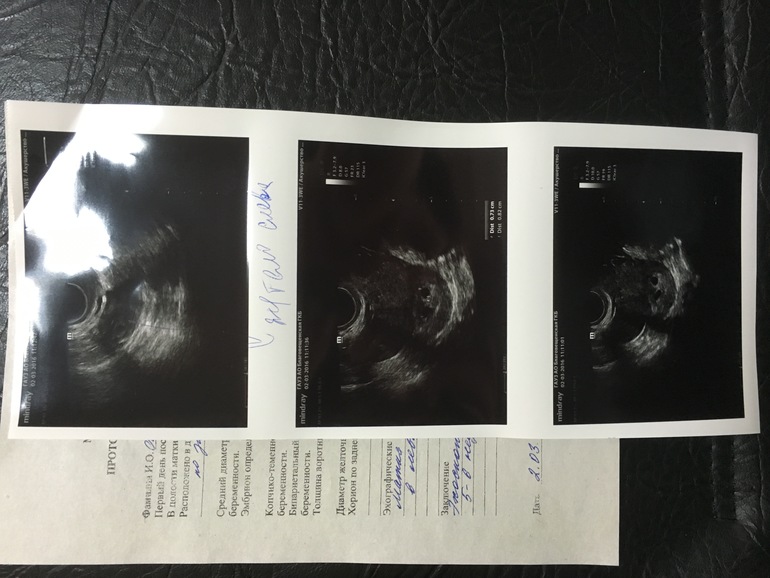

никакой,сейчас не мажет). Результат узи на фото, к сожалению

саму картинку она не смогла распечатать. Она вначале тихонько

спросила двойни в роду есть? потом сказала, что может и

гематома, но вряд ли, слишком правильная форма, округлая , и

шейка закрыта, но если это 2-е плодное яйцо, они разные же по

Поздравляю)) смотрю желтое тело тоже одно было и в левом яичнике?, я следующий раз на узи тоже 6+5 пойду как раз.Мне гематому тоже предположила, но говорит уж очень правильная форма для гематомы.

но и тогда должно быть 2 желточных мешка, узист что сказал? ПЯ рядом или на расстоянии, или может вы видели на мониторе??

если два плодных яйца, значит две овуляции. а вторая овулька подряд проходит через двое суток после первой. другой информации я не встречала... то ПЯ должны быть немного разного размера. плюс минус 1-3 дня. при более позднем сроке разница может быть более выраженной, потому что некоторые эмбриончики опережают свои сроки, некоторые день в день идут, а кто-то меньше своего срока растет

ну желтое тело точно одно, желточный мешочек пока один, но она говорит очень рано, через 10-14 дней будет уже точно, срок маленький, у меня овулька поздняя была, а вот тесты рано заполосатили, я удивилась, когда первый хгч 50 был, я максимум 20 ждала, как с дочкой, а второй хгч меня напугал, очень маленький прирост, зато через 24 часа, он вырос на стоько, на сколько до этого на 96....вобщем с математикой я не дружу, поэтому ничего не понимаю! На мониторе они недалеко друг от друга, я бы не сказала что на большом расстоянии?

значит разные ПЯ. потом повторите узи. посмотрят будет ли два плода, или все таки один останется. тут такие небылицы бывают... так что удачи, чтобы все отлично было!!!